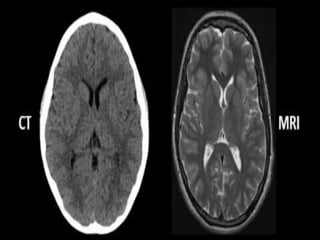

Difference between CT and MRI

MRI

 Granty of MRI consists of

small hole than CT scan.

 magnetic signals are used

 Good for visualization of

soft tissue

 High spatial resolution

 Typically takes 30-40

minutes

CT

 Granty of CT consists of

bigger hole than MRI scan.

 Ionizing radiation are used

organs and bony detail

 Long distance resolution

 Generally within 5 minutes